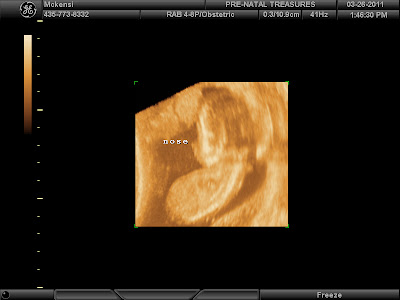

We have seen our baby and heard the heart beat twice.

I think its a girl, her heart beat is fast. (higher on the chart of what it could be.)